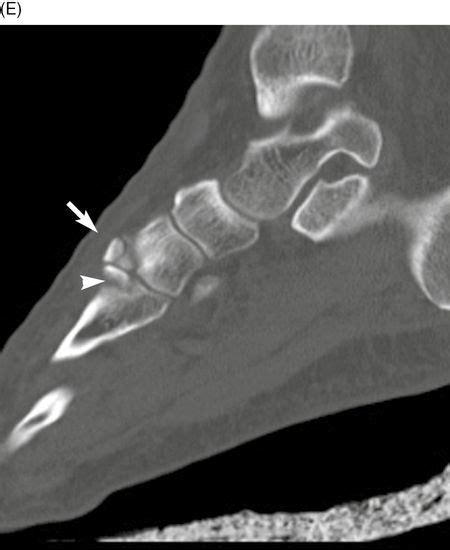

An avulsion fracture is a bone fracture which occurs when a fragment of bone tears away from the main mass of bone as a result of physical trauma. Long bone growth plate oblique fracture avulsion fracture functions of the skeletal system ball and socket joint. The patient began using a normal shoe at 10 weeks and resumed his running. An avulsion fracture is when a small piece of bone breaks and pulls away from a larger bone. Related online courses on physioplus. Learn how most avulsion fractures are treated. This typically involves the separation of the posterior tibial insertion of the pcl to variable d. This information will guide you through the next 6 weeks of your rehabilitation. In rigid shoe waiting for ortho consult. An avulsion fracture is a bone fracture which occurs when a fragment of bone tears away from the main mass of bone as a result of physical highly trained athletes can overcome this neurological inhibition of strength and produce a much greater force output capable of breaking or avulsing a bone. Part or all of the piece may break away. An avulsion fracture is also sometimes called a ballerina fracture or dancer's fracture because of the pointe position that ballet dancers. During an avulsion injury, a small fragment of bone at the base of the 5th metatarsal is pulled off by a strong ligament that is attached to this part of the bone. Avulsion fractures of the hip and. Great toe injury is common in athletes. Dx displaced avulsion fracture, base of big toe after worsening forefoot pain. While this might sound scary, these fractures are actually very easy to treat in most cases.